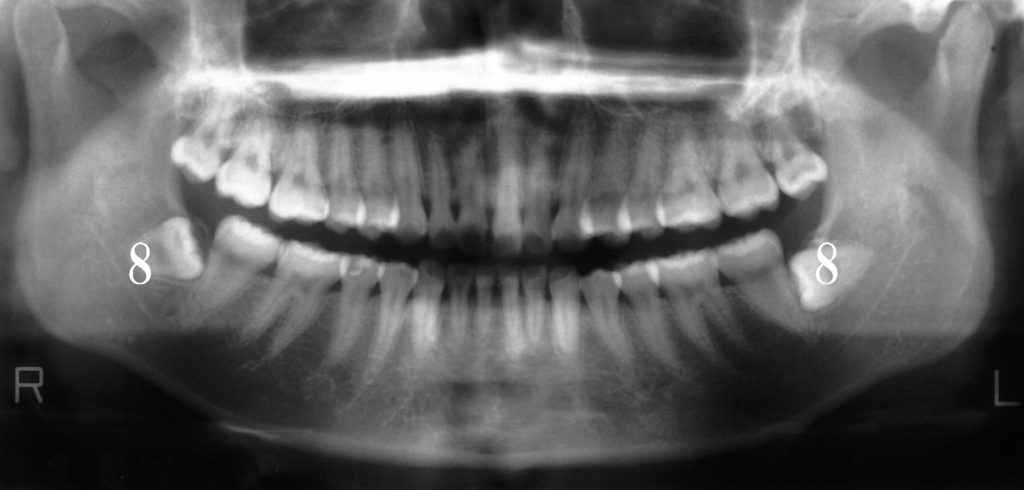

実際のパノラマレントゲンの見方

白く映っている部分は「歯」や「骨」です。

パノラマレントゲンでは、鼻の空洞・顎関節・下顎全体まで確認できます。

たとえば、下顎の左右に横向きで埋まっている親知らず(8番)を見ることができます。